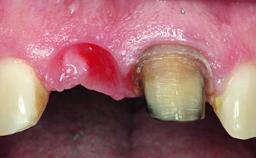

A 28-year-old patient presented at her general dentist’s office and complained about the appearance of her tooth 21. The patient had a history of trauma to this tooth. Endodontic treatment had been performed in the past and a crown placed on the tooth. A procedure to replace the old crown was performed by her dentist; however, a perforation on the middle third of the root occurred, and extraction of tooth 21 was suggested. Upon clinical and radiographic examination of the patient, who had been referred to us, replacement of tooth 21 by a dental implant appeared to be indicated.